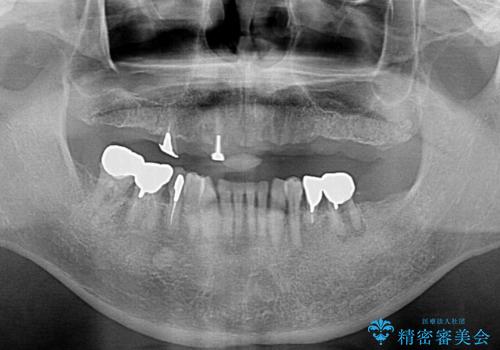

保存可能な2本の歯を用いて、マグネットデンチャー(磁性アタッチメントを用いた入れ歯)による治療を行いました。

下顎の治療に関しては、ご予算によりご希望されませんでした。

- ¥780,000 (根管治療×2本、土台×2本、磁性アタッチメント×2、金属床義歯)費用は治療当時の料金となります

予算を抑えて審美的に咬合を回復することができ、ご満足頂けました。

マグネット(磁石)により入れ歯がはずれにくく動揺しにくいため、入れ歯安定剤などを使うことなく食事やお話も問題なくできると喜んで下さいました。